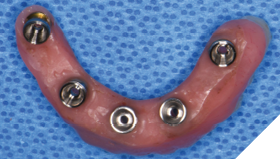

Three weeks later, the patient returned for treatment of the mandible (Figs. 13A, 13B). Teeth 22,23,24 were extracted and implants 19,21 and 27 were removed. A surgical guide with computer guided surgery was used to prepare the osteotomies and place the implants (Figs. 14A, 14B). Implants (Genesis Active – Keystone Dental) were placed in tooth positions 19,20,23,26 and 30. Allograft bone grafts were placed into the extraction sockets and all intraboney defects. Multiunit abutments were inserted on all implants and torqued to 30ncm (Fig. 15). The soft tissues were sutured closed. A rapid denture conversion system was used to efficiently convert a denture into a fixed provisional restoration.20 (EasyPro – Keystone Dental). This denture conversion system maintained the structural integrity of the denture while maintaining an esthetic provisional restoration (Figs. 16A-D).

Fig. 15